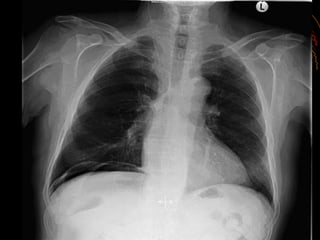

 Upright chest radiographs will show pneumoperitoneum

(ā€œfree airā€) in 80–90% of the cases.

 If pneumoperitoneum is identified on plain radiographs, there is

no need for further studies.